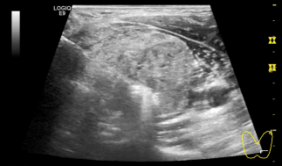

图 超声引导下甲状腺左叶实性结节穿刺活检+微波消融治疗